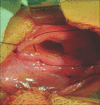

Figure 4

Left-sided diaphragmatic defect being repaired

Figure 5

Right-sided diaphragmatic defect being repaired